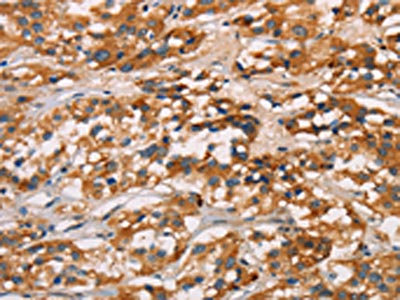

The image on the left is immunohistochemistry of paraffin-embedded Human thyroid cancer tissue using CSB-PA277650(CD80 Antibody) at dilution 1/50, on the right is treated with synthetic peptide. (Original magnification: ×200)

The image on the left is immunohistochemistry of paraffin-embedded Human gastric cancer tissue using CSB-PA277650(CD80 Antibody) at dilution 1/50, on the right is treated with synthetic peptide. (Original magnification: ×200)